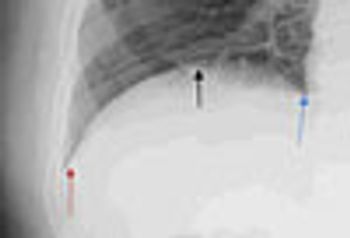

Phrenic nerve paralysis can present with chest wall pain, cough, and exertional dyspnea mimicking cardiac dyspnea. Fluoroscopy is the most reliable way to document diaphragmatic paralysis, and the sniff test confirms that abnormal hemidiaphragm excursion is due to paralysis rather than unilateral weakness.